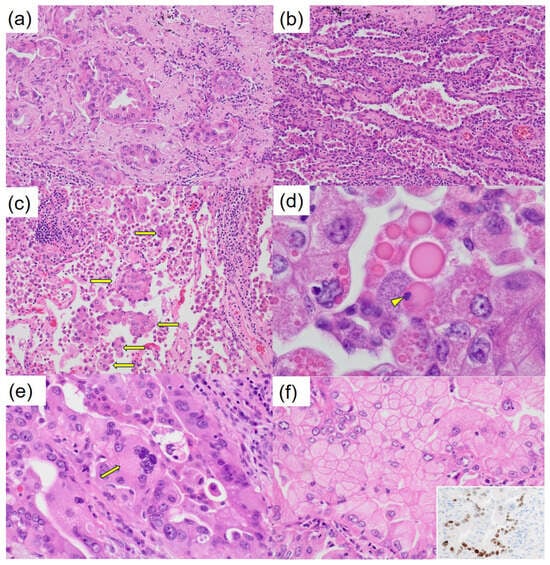

- Papadimitriou, J.C.; Drachenberg, C.B.; Brenner, D.S.; Newkirk, C.; Trump, B.F.; Silverberg, S.G. “Thanatosomes”: A unifying morphogenetic concept for tumor hyaline globules related to apoptosis. Hum. Pathol. 2000, 31, 1455–1465. [Google Scholar] [PubMed]

- Tachibana, M.; Koreyasu, R.; Kamimura, K.; Tsutsumi, Y. Pancreatic intraductal papillary mucinous neoplasm with hyaline globules (thanatosomes): Report of two cases. Int. Med. Case Rep. J. 2021, 14, 393–399. [Google Scholar] [CrossRef] [PubMed]

Tachibana, M.; Ito, Y.; Fujikawa, R.; Tsukamoto, K.; Uehara, M.; Kobayashi, J.; Hayashi, T. Lung Adenocarcinoma Exhibiting Thanatosomes (Hyaline Globules), Cytoplasmic Clearing, and Nuclear Pleomorphism, with a KRAS Mutation. Diagnostics 2025, 15, 894. https://doi.org/10.3390/diagnostics15070894